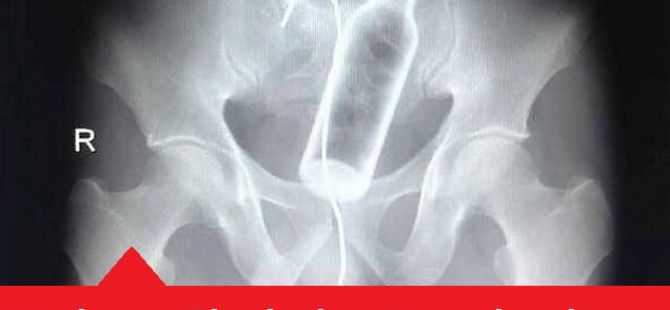

02 Ekim 2015 Cuma 18:33Malum Bölgelerine Kazayla Giren Nesneler Sonucu Acile Kaldırılmış İnsanların 15 Röntgen Görüntüsü Bu nesnelerin orada olmasının mantıklı hiçbir alakası yok. Büyük ihtimalle bir kaza sonucu bu durum oluşmuştur. Aksini düşünmek bile istemiyorum. Foto Galerimizin devamını görmek için Lütfen sonraki sayfaya geçiniz..